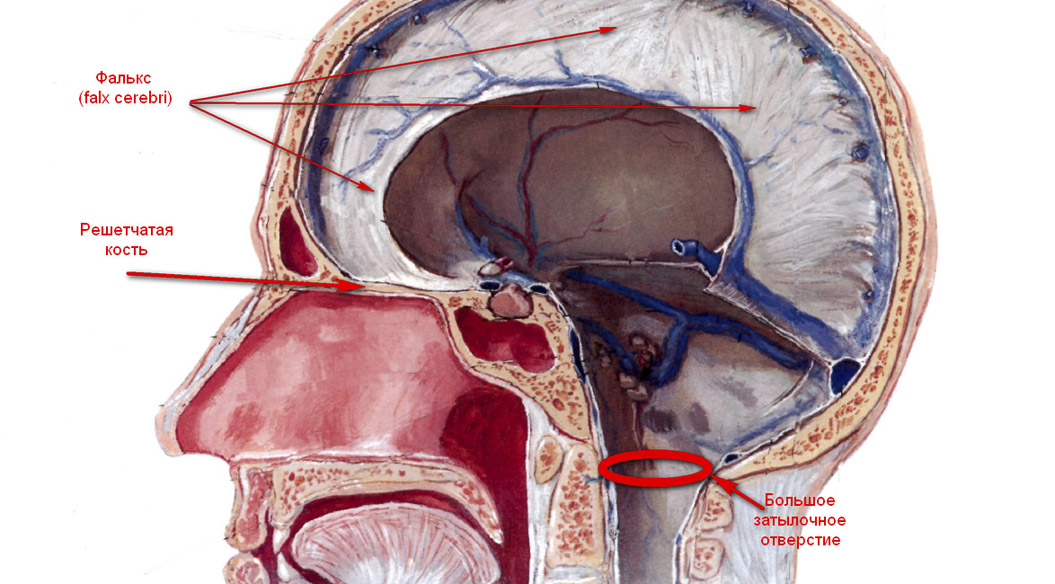

Два полушария головного мозга, мозжечок и продолговатый мозг расположены в черепе и фиксируются в нем сложной системой соединительно-тканных оболочек, образующих структуры поддерживающих и охватывающих отделы мозга с разных сторон связок и наметов. Одновременно тонкие, но прочные, они жестко фиксированы к костям черепа, образуют систему венозных синусов, которые участвуют в кровоснабжении мозга.

Левое и правое полушария головного мозга отделены одной из таких оболочек, которая получила название фалькс (falxcerebri— лат.) Из своего основания, где расположен венозный синус, она как бы врастает между полушариями с внутренней поверхности черепа, огибая своим тонким краем, упирается в мозолистое тело на всем протяжении, от лобной до затылочной части. Мозолистое тело (corpuscallosum— лат.) содержит множество нервных волокон, обеспечивающих межполушарные связи, объединяя в единую систему функции правого и левого полушария.

В затылочной части мозжечок отделен от больших полушарий своими оболочками, т. н. наметом мозжечка, который с обеих сторон охватывает своим тонким краем стволовые структуры мозга, в которых расположены самые древние жизненно важные центры — сосудодвигательный и дыхательный. Все это вместе заключено в твердую мозговую оболочку, которая обильно снабжена сосудами и прилежит к внутренней поверхности черепа.

Большое затылочное отверстие, через которое выходит спинной мозг, окружает основание продолговатого мозга со всех сторон чуть ниже сосудодвигательного и дыхательного центров. Между мозгом и краями отверстия имеется около сантиметра свободного пространства.

Рис. 1.

Рис. 2. Передняя черепная ямка (Ф. Неттер. Атлас анатомии человека. М. 2003).

Рис. 3. Повреждение обонятельных нервов у края решетчатой кости (Ф. Неттер. Атлас анатомии человека. М. 2003).

Рис. 4. Повреждение колена мозолистого тела (Ф. Неттер. Атлас анатомии человека. М. 2003).